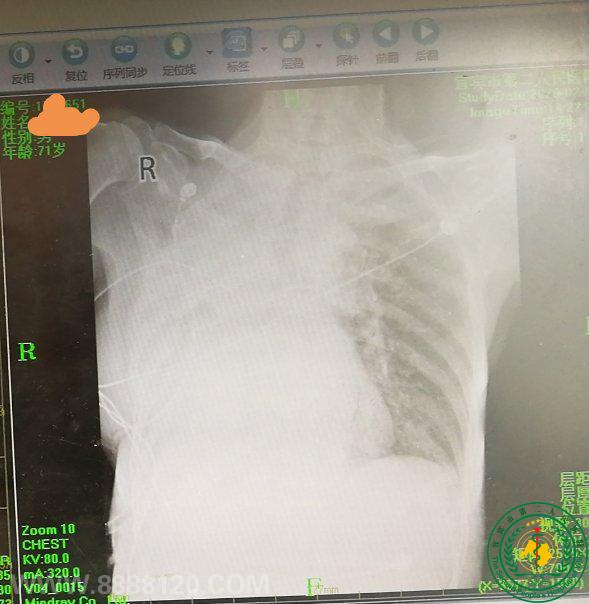

新冠“发热”阴影笼罩下1例重症脓胸患者成功救治的艰辛历程

新冠“发热”阴影笼罩下1例重症脓胸患者成功救治的艰辛历程25620